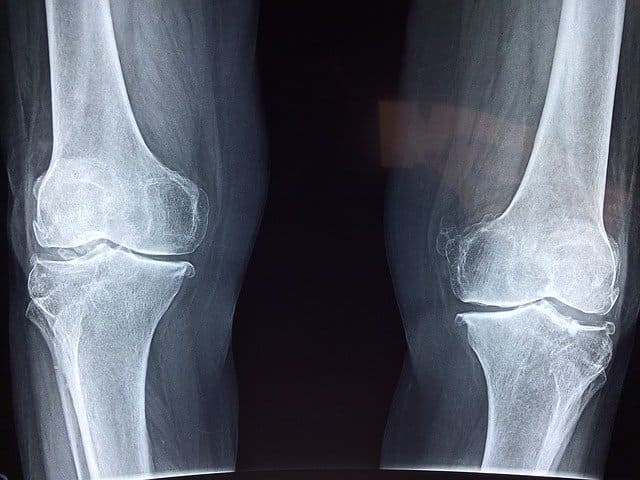

골다공증은 천천히 우리 몸에 있는 관절과 뼈를 약하게 만드는 질병을 말합니다. 40세 이후부터 남녀 불문하고 골밀도가 낮아진다고 합니다! 특히 여성의 경우 매년 골밀도가 1.5 ~ 2% 감소한다고 합니다. 뼈에 미세한 구멍이 생기게 되고 이로써 작은 충격에도 쉽게 골절이 되게 됩니다. 골다공증은 노인들 사이에서 가장 흔한 질병 중 하나입니다. 유전 적 요인, 조기 폐경, 장기간 스테로이드 사용으로 골다공증이 발병할 수 있고, 알코올 및 흡연으로 인해 골다공증이 어린 나이에도 갑작스럽게 발생하는 경우도 있습니다. 그러나 대부분의 골다공증은 노화로 생기는 질병이고, 증상이 없기 때문에 외부 충격으로 골절된 후 자신이 골다공증이란 것을 발견하는 경우가 많습니다.

골다공증 특성상 초기에 어떠한 증상도 없습니다. 극히 일부의 경우 요통이 발생하지만 보통 골밀도 검사에서 발견됩니다. 골다공증이 진행됨에 따라 허리 통증이 심해지고 신장(키)이 감소하며 등이 구부러집니다. 또한 골반, 팔, 손목이 약간 부딪쳐도 뼈가 부러 질 수 있습니다!